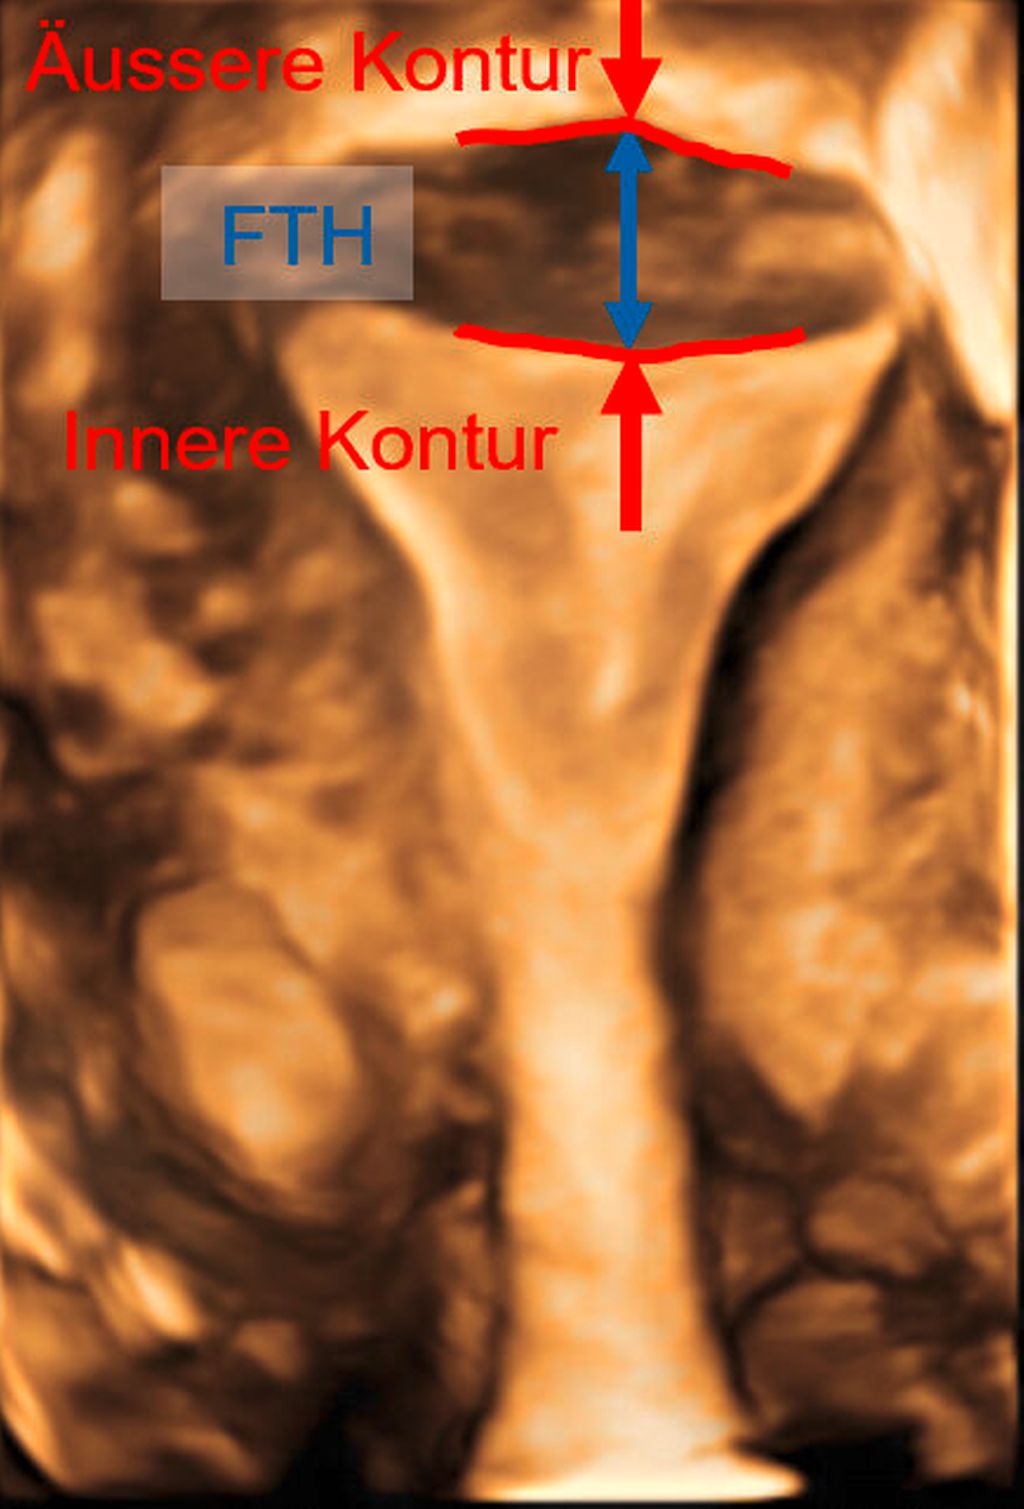

Abb. 2: Multiplanare Rekonstruktion der Koronarebene. Die äussere und innere Funduskontur sind rot eingezeichnet. Die Fundusdicke («fundal thickness», FTH) lässt sich ausmessen

Die Untersuchung wird idealerweise bei hoch aufgebautem Endometrium durchgeführt. Nach Erstellung der Koronarebene kann sowohl die äussere als auch die innere Uteruskontur dargestellt und die Fundusdicke («fundal thickness», FTH) bestimmt werden (Abb. 2). Eine allfällige Septierung ist dabei einfach erkennbar und mittels eines Messkreuzes leicht objektivierbar. Dies lässt sich einfach konstruieren: Zunächst wird eine Hilfslinie zwischen den beiden inneren Tubenostien eingezeichnet (sog. Interostiallinie). Nun kann kranial davon die Fundusdicke (bis zur Serosa) und kaudal davon die Länge des Septums sowie der Winkel der Septumspitze bzw. Carina ausgemessen werden (Abb. 3). Je nach Klassifikationssystem unterscheiden sich hier die Definitionen bzw. Massangaben, welche zur Diagnose einer Fehlbildung nötig sind. Während die ESHRE-ESGE-Guideline relativ «laxe» Kriterien vorschlägt, unter deren Anwendung viele Patientinnen die Diagnose eines Uterus (sub-)septus erhalten würden (bis zu 80%!), landen gemäss ASRM-Klassifikation viele Patientinnen in einer «Grauzone». Hier bewähren sich die CUME-Kriterien, mit deren Hilfe eine Einteilung gelingt, die am ehesten der tatsächlichen Prävalenz entspricht, und dies bei entsprechender Trennschärfe.8 Die vorgeschlagenen Kriterien zur Diagnose eines Uterusseptums sind eine Septumlänge von mindestens 10 mm, ein Winkel von <140° und ein Verhältnis Septum:Fundusdicke von >110% (Abb. 4, Tab. 1).